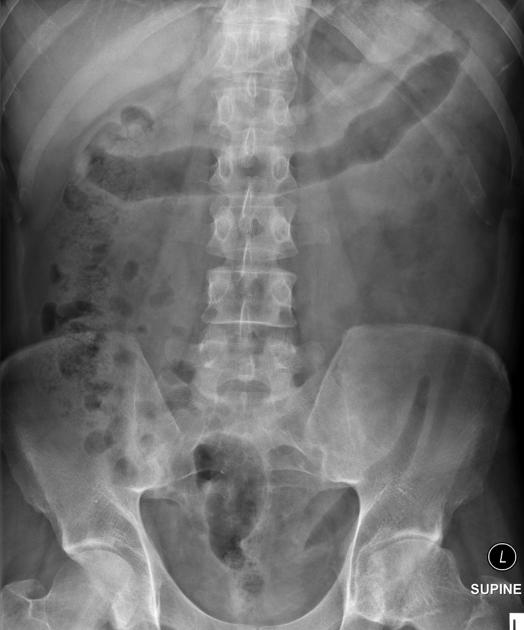

D – This is an Abdominal X-Ray taken on ….., of the following patient….. Is there a previous AXR to compare to?

R – Commenting first on the quality, it is not rotated, there is adequate field of view, the projection is anterior-posterior, the patient is lying supine and it is adequately exposed as I can see the vertebral bodies clearly

“On initial inspection, there appears to be signs of inflammation in the transverse colon, but I will proceed to go through it systematically.”

B – Looking at the film, the small bowel is not visible. There is loss of haustra markings in the transverse and descending colon. This looks like the “lead-pipe” sign which is suggestive of inflammation. There is also evidence of faecal loading in the ascending colon. The bowels are not dilated and no sign of obstruction.

O – Looking at the other organs, there is no basal lung consolidation. No hepatobiliary abnormality. The urinary system looks normal and no evidence of a psoas muscle abscess.

B – There are no fractures to the bones. There is a lateral curvature of the spine but the vertebrae appear normal. There is normal spacing of the sacroliliac and hip joints.

C– There are no other calcifications or foreign bodies.

In summary this AXR shows some inflammatory changes in the large bowel with loss of hautra markings and faecal loading in the ascending colon. It would be useful to see if there is previous to compare to in order to see if this is a new finding or chronic.

Lead pipe colon and faecal loading in ascending colon – found in ulcerative colitis